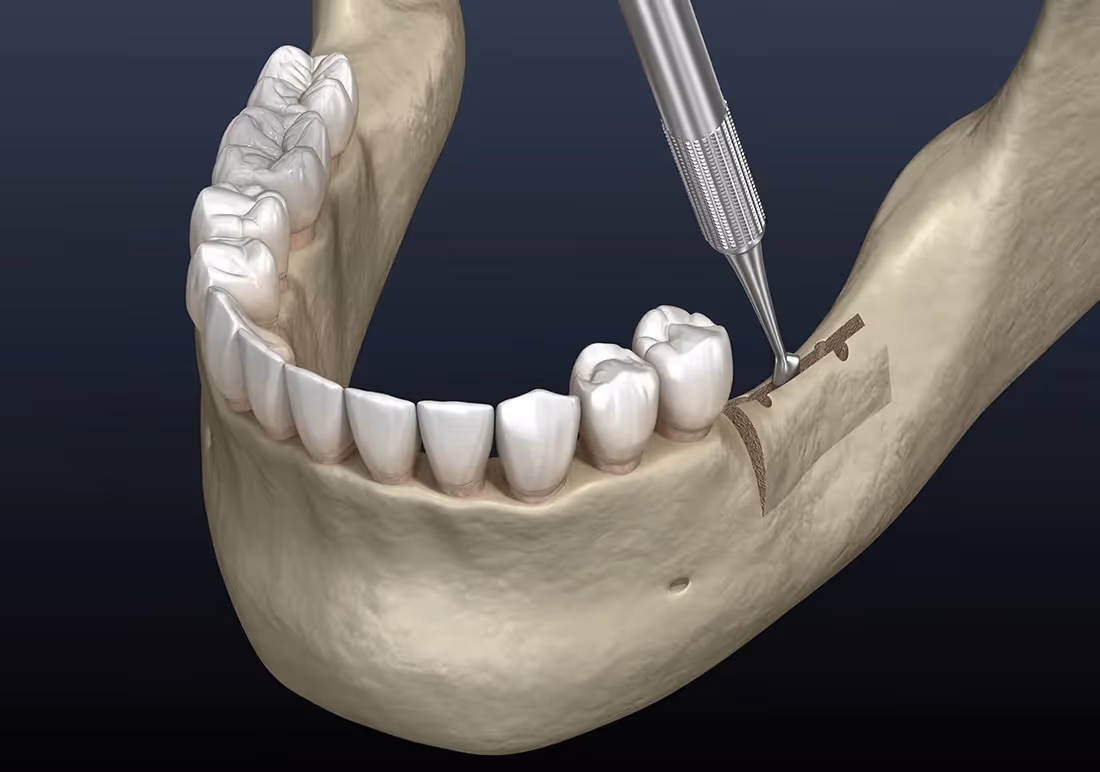

If you’ve struggled from jaw bone loss due to missing teeth, you’re not alone, and there’s a solution to get you smiling again. A ridge augmentation recreates the natural contour of the gums and jaw bone, restoring its form and creating a solid foundation for implants.

After tooth extraction, the jaw bone may need to be rebuilt and reshaped to make sure that your mouth can accommodate a dental implant, or for aesthetic purposes. Not everyone needs ridge augmentation, but it’s often done immediately after tooth extraction to avoid the need for another surgery. If your oral surgeon believes that your jaw bone may need strengthening, it’s a good idea to get ridge augmentation during your tooth extraction procedure.

The Ridge Augmentation Process